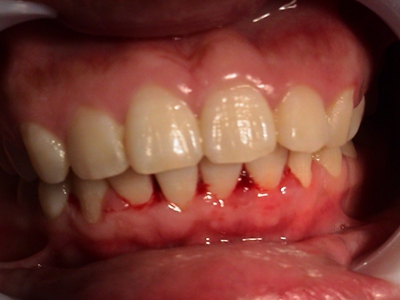

牙龈

红肿

戈登热牙龈红肿出血图

登革热患者可以发生不同程度的出血现象,包括牙龈红肿出血,牙龈边缘渗出鲜红色的血液,同时可伴有发热、头痛、肌肉及关节痛、极度乏力、恶心、呕吐等症状。

充血

戈登热牙龈充血牙齿上带血图

登革热会使毛细血管通透性增加导致明显的血浆渗出,出现牙齿上带血,也可能导致其他情况的出血情况,比如皮下出血、注射部位瘀点瘀斑、鼻出血等。

出血

登革热牙龈出血图

登革热患者会出现不同程度的出血现象,可表现为牙龈出血,多为鲜红色,出血量一般较少,牙龈多无红肿。患者常伴有高热、头痛、呕吐、腹泻等全身症状。